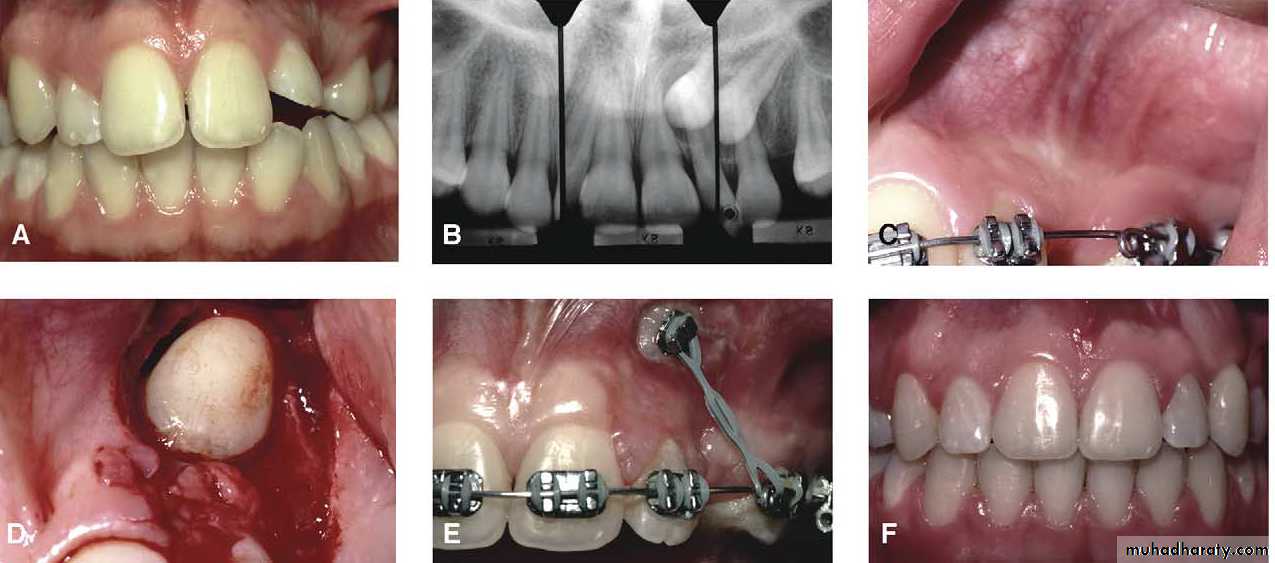

Transplantation and surgical repositioning

The success rate with transplantation is highest for unerupted teeth which have open apices because of the possibility of revascularization .It is essential to establish that there is sufficient space to accommodate the canine crown. minimal space deficiency may be overcome by grinding of the crown , but otherwise orthodontic therapy may be required to move the premolar distally .

Mosul university- College of dentistry-oral & maxillofacial surgery department

The canine should be extracted carefully and transferred to the surgically prepared socket in the dental arch with the minimum of delay.

It is preferable that the root surface should not be touched either with instruments or fingers as the viability of the cementum and periodontal membrane remnants will determine the success of the transplant. The tooth is stored under the flap until the new socket is prepared .

Root filling is not attempted so as to reduce handling of the tooth . The transplanted tooth should be splinted in its new position for a month after the operation .